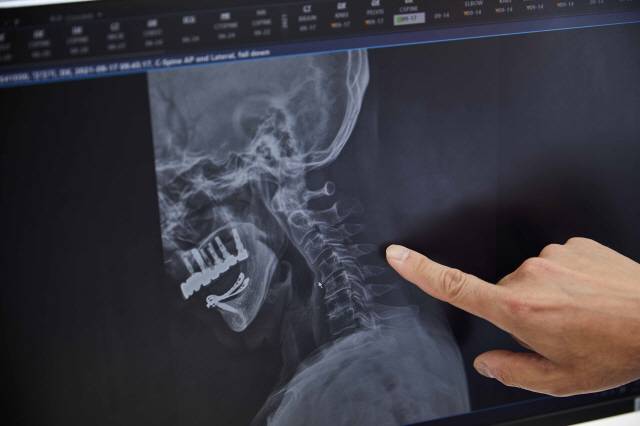

사무실에서 하루 종일 모니터를 보며 일하는 직장인 김모(28·서울 용산구)씨는 자주 목주변 근육이 경직돼, 결국 정형외과로 향했다. 정상적인 목 뼈는 C자 곡선을 유지해야 하는데, 김씨는 일자를 넘어 역 C자 형태에 접어든 것으로 확인됐다.

사무직 직장인은 물론, 휴대폰 사용이 일상이 된 현대인에게 '거북목'은 고질병이 됐다. 김씨 처럼 목뼈가 역 C자형이 됐을 때, 생활 습관을 교정하면 다시 C자 곡선으로 되돌릴 수 있을까?